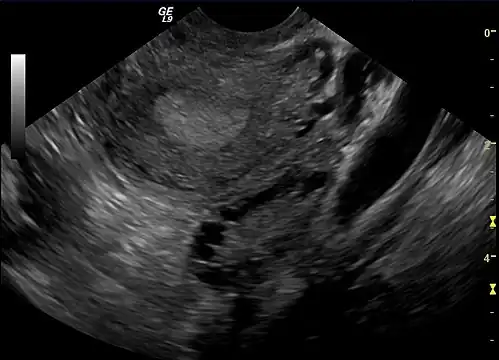

Gynecologic ultrasonography first looks for small ovarian follicles.[104] To count as polycystic ovaries, at least 20 follicles need to be present, smaller than 9 mm. This used to be 12 in older diagnostic criteria.[99] A less clear marker of PCOS is enlarged ovaries.[104] Ovary need to be at least 10 cm3 to count.[99] For sexually active individuals or those that agree, a transvaginal ultrasound approach is preferred. Alternatively, AMH levels can be tested in the blood.[104] Laparoscopic examination may reveal a thickened, smooth, pearl-white outer surface of the ovary. This would usually be an incidental finding if laparoscopy were performed for some other reason, as it would not be routine to examine the ovaries in this way to confirm a diagnosis of PCOS.[107]

-

Transvaginal ultrasound scan of polycystic ovary -

Polycystic ovary as seen on sonography